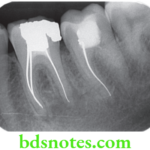

Endodontic Sealers And Obturating Materials Notes

Endodontic Sealers And Obturating Materials "What are endodontic sealers and obturating materials? A detailed question and answers guide" Following the cleaning, debriding and enlarging of the root canals, the canals spaces are sealed or obturated to prevent reinfection and colonization by bacteria. Why obturate canals? Microorganisms and their byproducts are the … [Read more...] about Endodontic Sealers And Obturating Materials Notes